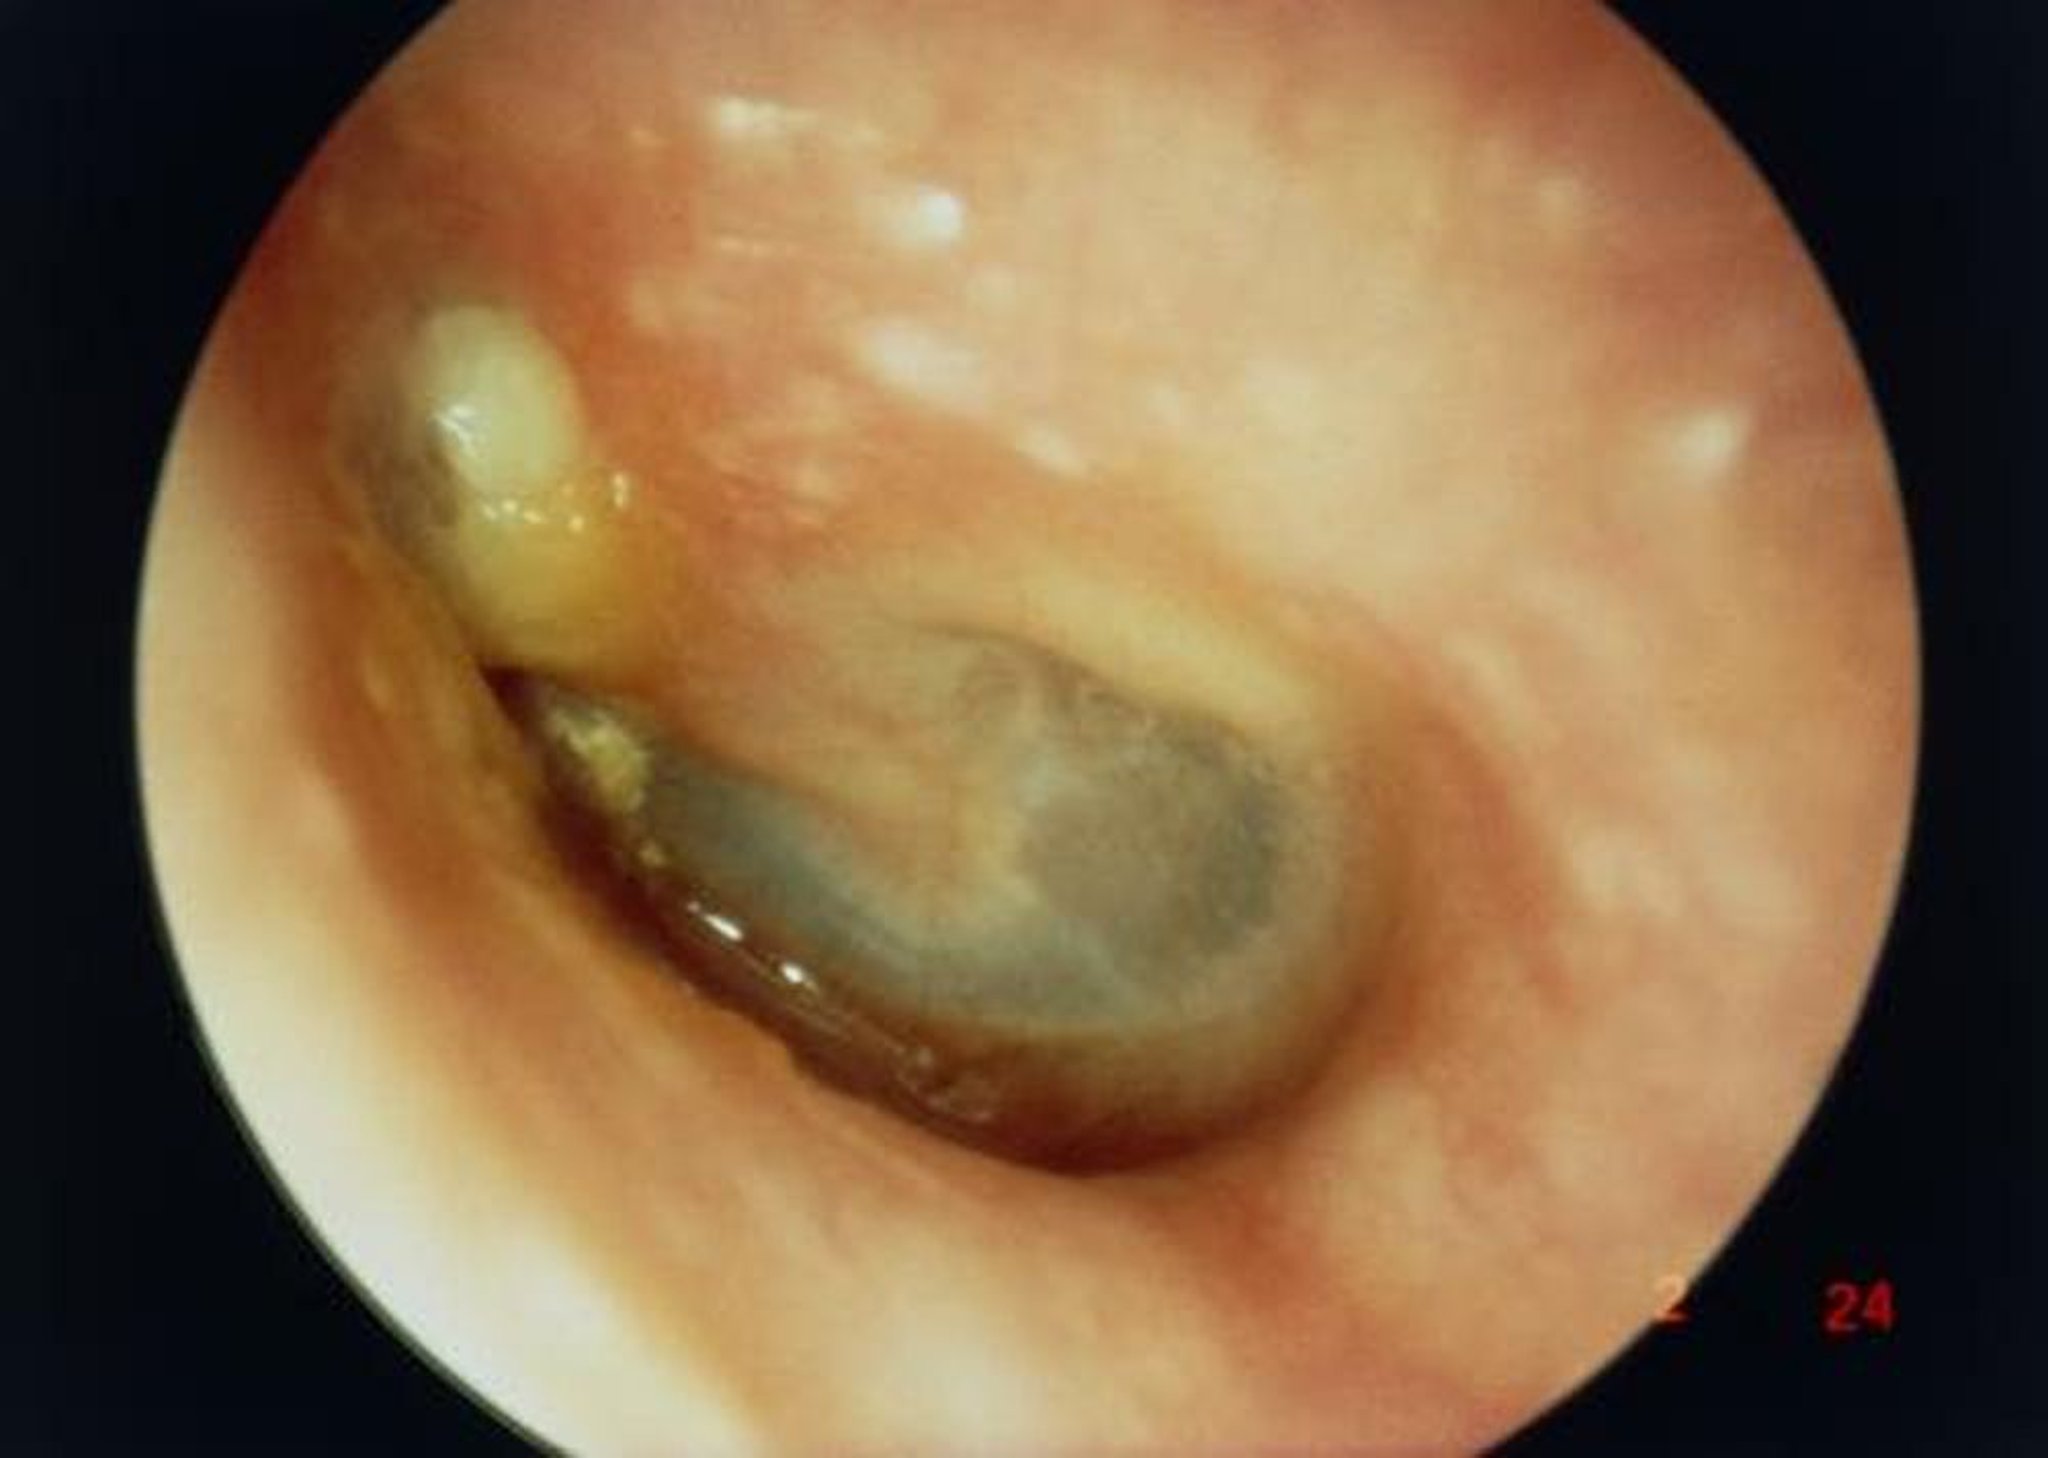

Colesteatoma

En esta imagen, la vista a lo largo del conducto auditivo externo muestra un gran colesteatoma (masa blanca sobre la cara superior izquierda de la apófisis corta del martillo) que da lugar a una perforación de la membrana timpánica.

PROFESSOR TONY WRIGHT, INSTITUTE OF LARYNGOLOGY & OTOLOGY/SCIENCE PHOTO LIBRARY